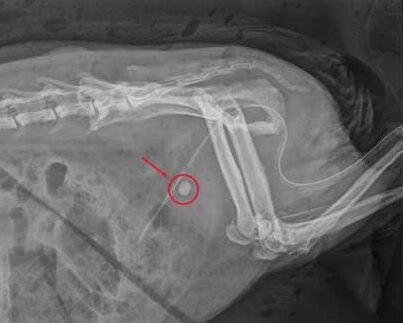

Nach Röntgenaufnahmen war schnell klar: Ein großer Harnstein hatte sich im Bereich des Beckens festgesetzt. Der zusätzliche Ultraschall zeigte freie Flüssigkeit im Bauchraum. Das ist ein Hinweis auf eine mögliche Harnblasenruptur. Kann der Urin nicht mehr abfließen, besteht im schlimmsten Fall die Gefahr, dass die Blase reißt. Der Harn kann sich aber auch bis in die Nieren zurückstauen und zum Nierenversagen führen. Es musste also schnell gehandelt werden.

Bei Stöpsel war der Harnstein ziemlich groß, fast einen halben Zentimeter, und in einer äußerst ungünstigen Position in der Harnröhre verkeilt. Er war nicht mehr in der Blase, aber auch noch nicht in der Nähe der Penisspitze, wo man ihn hätte leichter entfernen können. Eine Operation war bei dieser Lage nicht möglich. Judith Führers Ziel war es also, den Stein zunächst vorsichtig mit einem Katheter in die Blase zurück zu spülen. Das birgt bei männlichen Meerschweinchen zusätzlich Schwierigkeiten, denn sie haben zwei Öffnungen am Penis, man muss also sehr genau wissen, wohin man den Katheter führt.